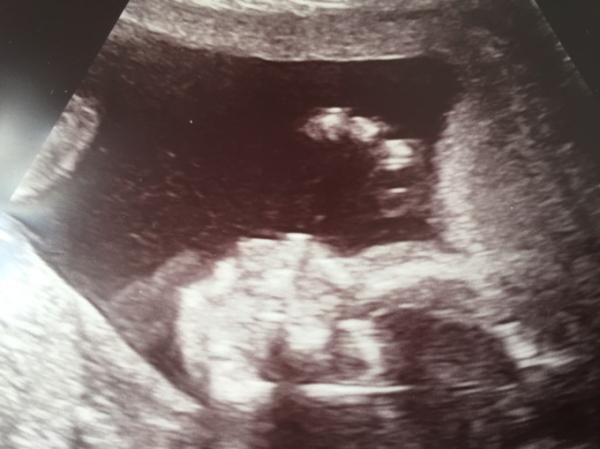

Hallo zusammen, wir waren gestern auch zur Feindiagnostik in unserer Klinik...Grund waren 2 White Spots. Es ist alles wunderbar, keine white Spots mehr zu sehen gewesen Und auch sonst keine Anzeichen für Anomalien. Es ist alles super entwickelt und so, wie es sein soll. Krümelchen ist ca. 23 cm groß und wiegt 369 g Die Bilder waren aber nur minimal besser als letzte Woche, er hat aber diesmal ein bisschen länger still gehalten...kleiner Zappelfisch Wir haben uns zwar versucht, nicht verrückt zu machen, aber wir sind nun trotzdem unendlich erleichtert. Ich drücke allen die Däumchen, die diese Untersuchung noch vor sich haben. Schönes WE euch allen

Bild zu Feindiagnostik geschafft - Forum für Januar - Mamis